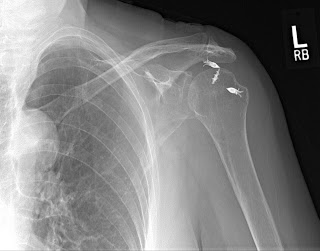

Each patient has had an arthroscopic rotator cuff repair by another surgeon. The first set of films demonstrate that the metal anchors have pulled out of the very soft bone and as a result the tendon has retorn after a rotator cuff repair. This failure was within the first year. This patient was in therapy for many months and could never lift her arm after the repair. Her pain was considerable and she became very unhappy with the situation and eventually came to me for help. A simple x-rays tells the whole story. No MRI needed here. The only set of post operative x-rays done were those done in my office about a year after surgery.

The fact that the anchors are now out of the bone, floating in the joint, indicate that this mechanism of failure. Rotator cuff tendon quality also affects the success of a tendon repair. Poor quality tendon in more likely to retear. Larger tears involving more than one of the 4 rotator cuff tendons will have a higher failure rate as well. Patients over 65 years of age and chronic tendon tears will also have higher rates of failure.

Notice the metal anchors above that seem to be floating in the joint. This foreign body in the joint is very painful. I did surgery on the above patient to remove the anchors arthroscopically. Her pain improved, but her function never recovered. Although I thought she would have done well with a reverse total shoulder replacement, she said that she had enough surgery. I advised her about the limits of surgery under these conditions and, after surgery, she was happy that her pain was improved.